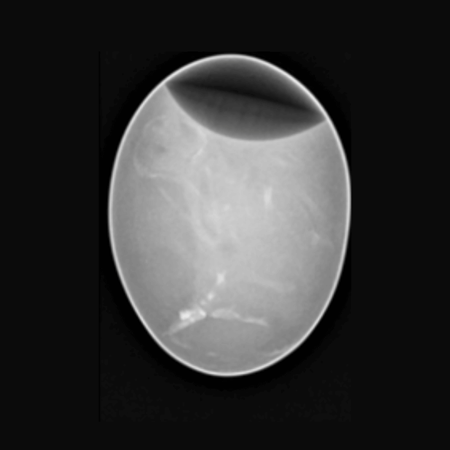

Chicken Egg. Image Credit: Scintica Instrumentation Inc